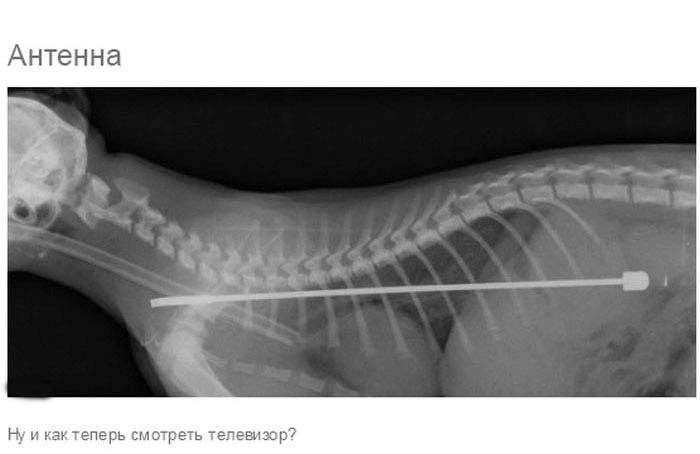

» Что может оказаться в желудке собаки

Что может оказаться в желудке собаки